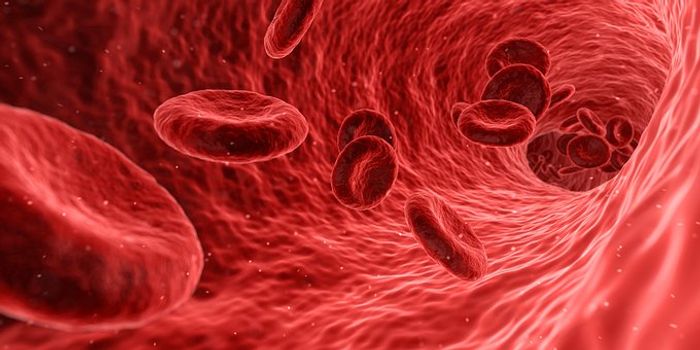

FEB 23, 2019CardiologyThe circulatory system is a complex collection of the heart and its many chambers, and the vessels that move blood aroun ...